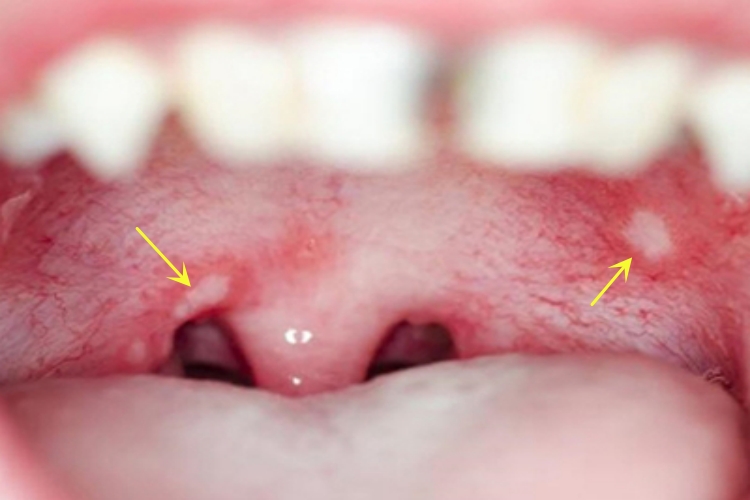

口腔溃疡可导致口腔上腭出现较小的白色斑片,黏膜逐渐出现溃疡,多呈圆形或椭圆形,随着病情的进展,溃疡点可逐渐增大,伴有明显疼痛感。

口腔溃疡是由黏膜上皮的炎症、损伤或凋亡引起的,可能是由于局部刺激、感染等导致。在上腭区域,可能受到刷牙、过热食物、酸性食物、细菌感染等所引起的刺激,进而引发免疫细胞的聚集,释放炎症介质,导致黏膜组织损伤和溃疡形成。